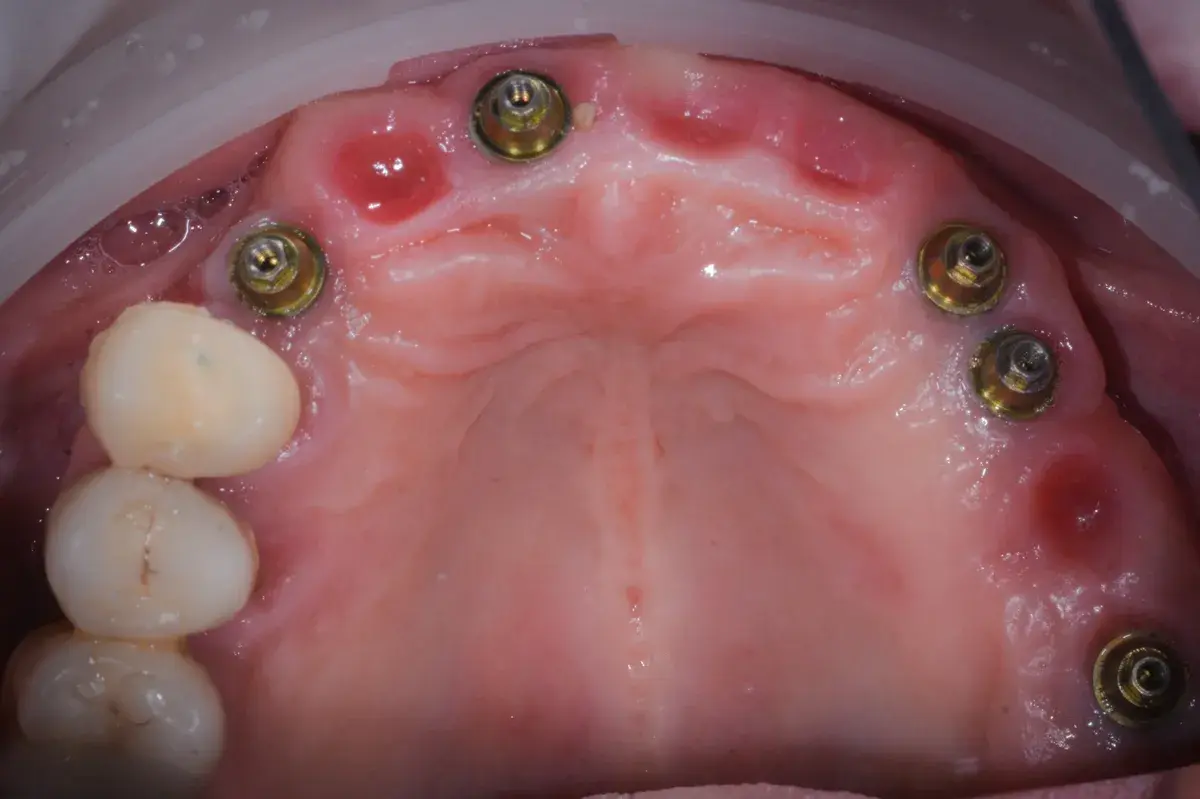

Cresta atrofica in zona 4.6 con difetto osteo-mucoso e cheratinizzata quasi assente: Bonebending 4.0 e impianto in unica seduta. Risultato a 3 mesi.

Caso clinico: espansione crestale ERE con impianto immediato e rigenerazione simultanea. Da ponte fallito a impianto in un'unica seduta.

Caso clinico di carico immediato su rialzo crestale del seno mascellare con espansori. Espansione apicale, stabilità >50 Ncm, provvisorio immediato e co...

Esplora il protocollo di espansione apicale, una strategia innovativa per ottenere stabilità ottimale e preservare l’integrità dei tessuti ossei e molli.